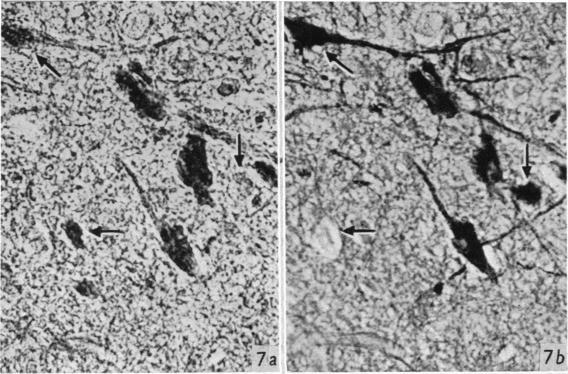

Hypothalamic neurosecretion in the dog and cat, with particular reference to the identification of neurosecretory material with posterior lobe hormone.

J Anat. 1955 Jul;89(3):301-16.